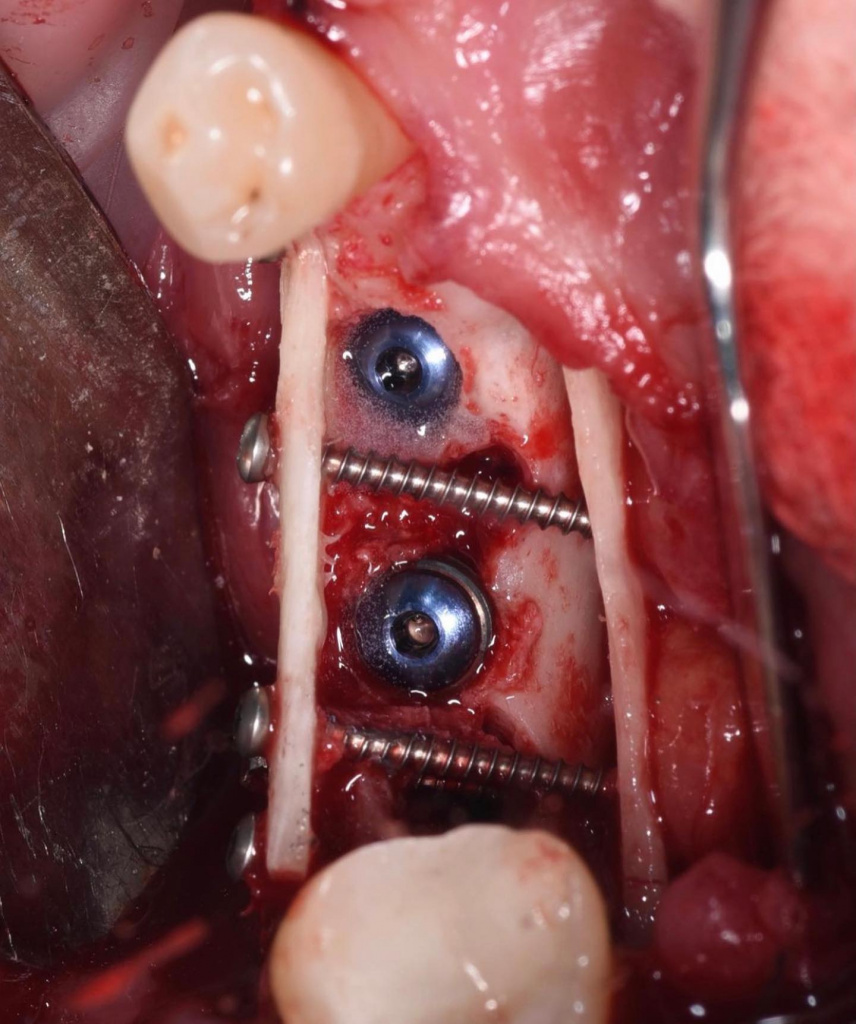

- Фиксация блоков

- Установка имплантатов AnyRidge

- Заполнение пространства между блоками аутостружкой, смесью ауто- и алло-материалов